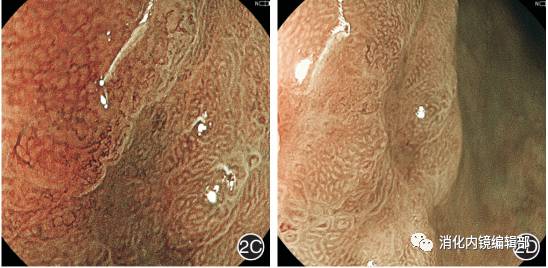

图2  病理诊断为低级别上皮内瘤变的病变镜下特征2A:普通白光胃镜可见胃窦前壁近胃角处一1.0 cm×1.0 cm大小的Ⅱc型病变;2B:白光单独放大可见病变表面微血管和微腺管结构欠规则,边界不清楚;2C:BLI-contrast放大下观察可见病变表面微结构欠规则,可见异性增生的血管,病变与组织周围边界清楚;2D:BLI-bright放大下可见病变表面微腺管及微血管结构排列不规则,病变与周围组织边界清楚